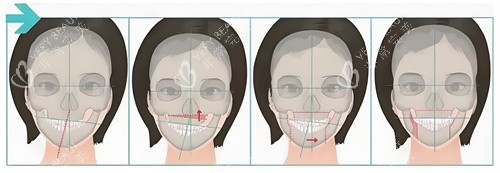

"16-18岁做手术,就像在春天播种,秋天准能收获。"武汉大学口腔医院主管医师王芳,用这个比喻解释黄金期的好处。她手机里存着上千组对比照:术前"鞋拔子脸",术后"标准鹅蛋脸",差别大得像换了个人。

骨骼可塑性强

这个年龄段的上颌骨像"橡皮泥",医生轻轻一推就能归位;下颌骨像"软陶",容易塑形。王医生做过统计:黄金期手术的患者,90%术后3个月就能正常咀嚼,而成年患者得半年。

王芳医生给他的方案是"上颌前徙术":从口腔内切个小口,把上颌骨整体前移3mm。手术用了2小时,出血量不到50ml。术后第5天,小凯就能吃面条;***0天,他已经敢对着镜子咧嘴笑了。